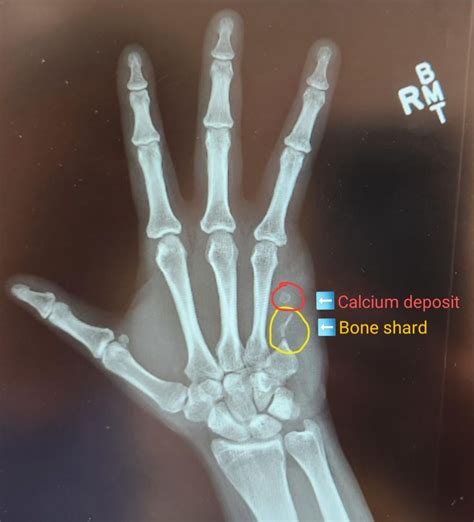

A doctor will typically perform an X-ray to determine the location and severity of the fracture. Depending on the results, your treatment plan might involve: